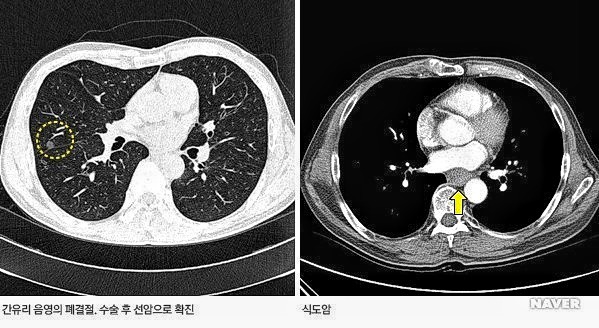

9. 진단질병

몸의 거의 모든 질병이 검사 대상이 된다. 특히 두경부, 폐, 식도, 종격동, 간, 위장관, 뼈 등의 거의 모든 장기의 종양성 질환 및 외상을 파악하는 데도 도움이 된다.

CT 촬영장치

CT 촬영결과